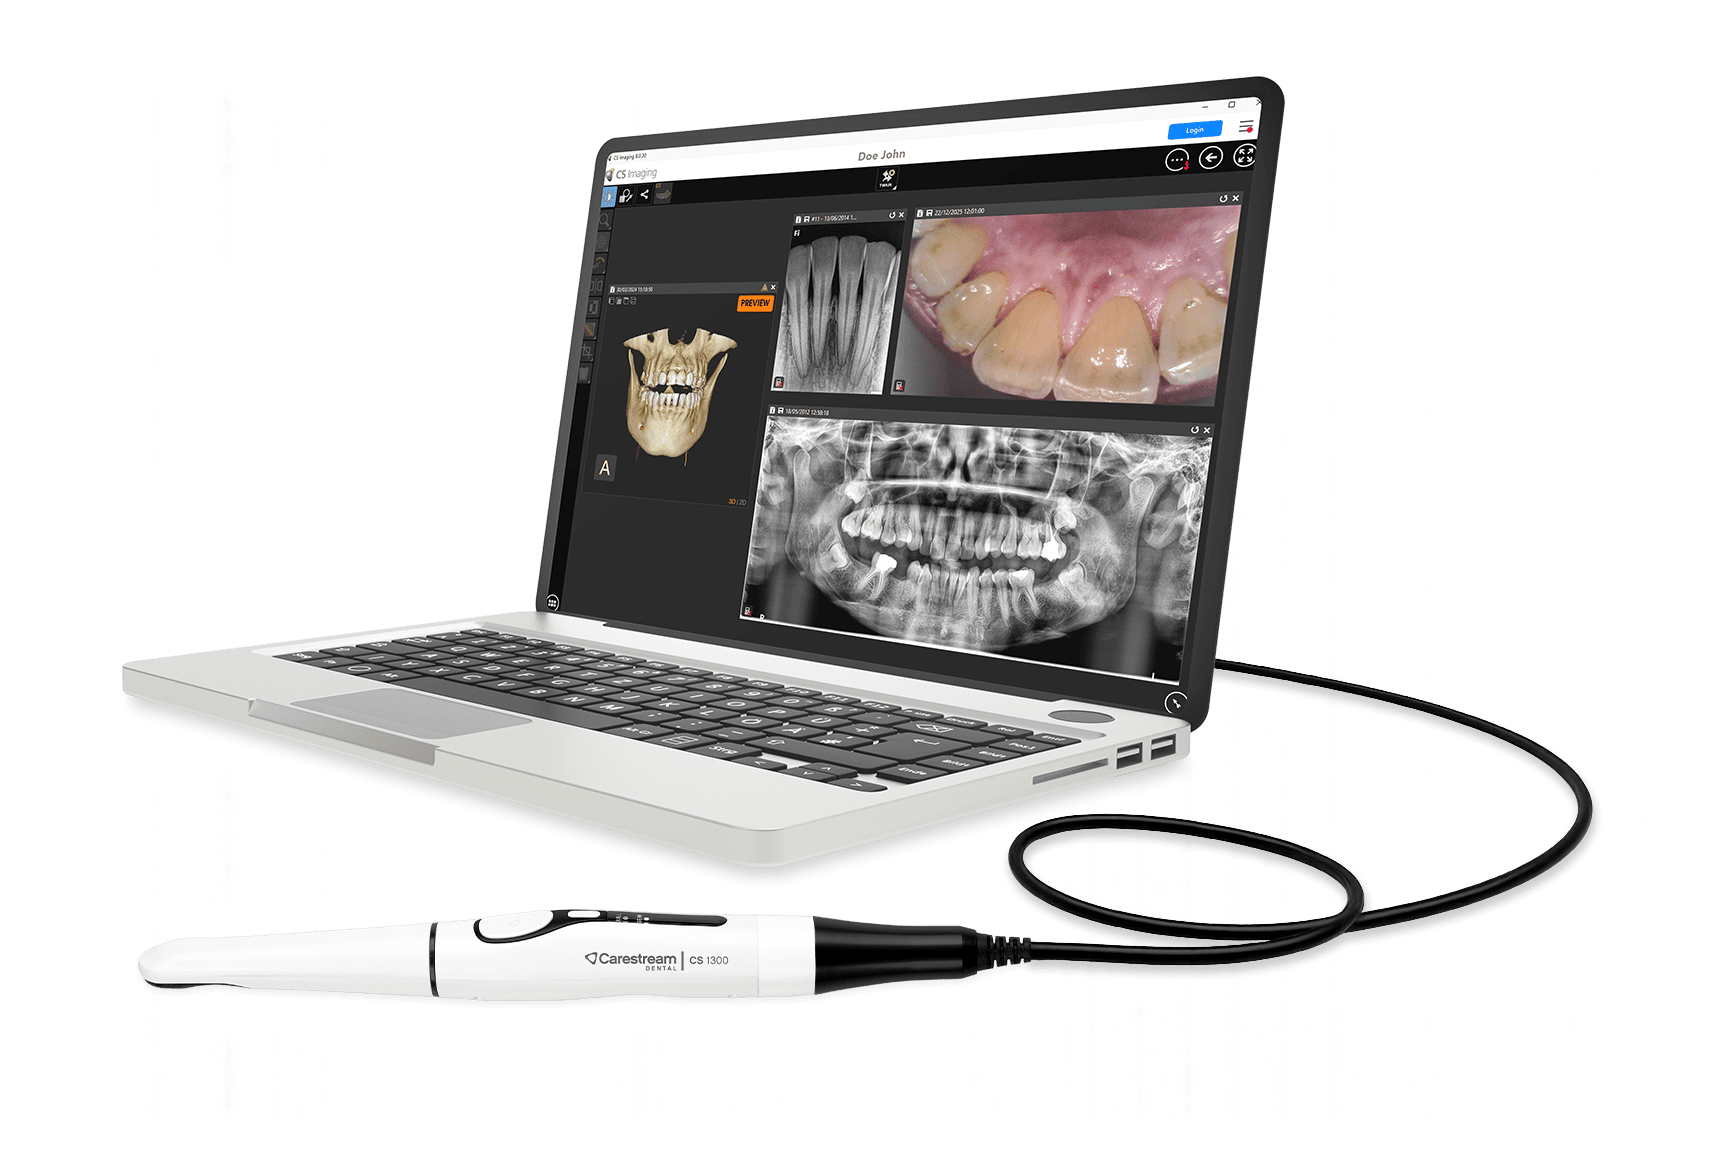

Στην εταιρεία μας λειτουργεί Showroom με τα μηχανήματα της Carestream Dental, των οποίων είμαστε εξουσιοδοτημένοι αντιπρόσωποι.